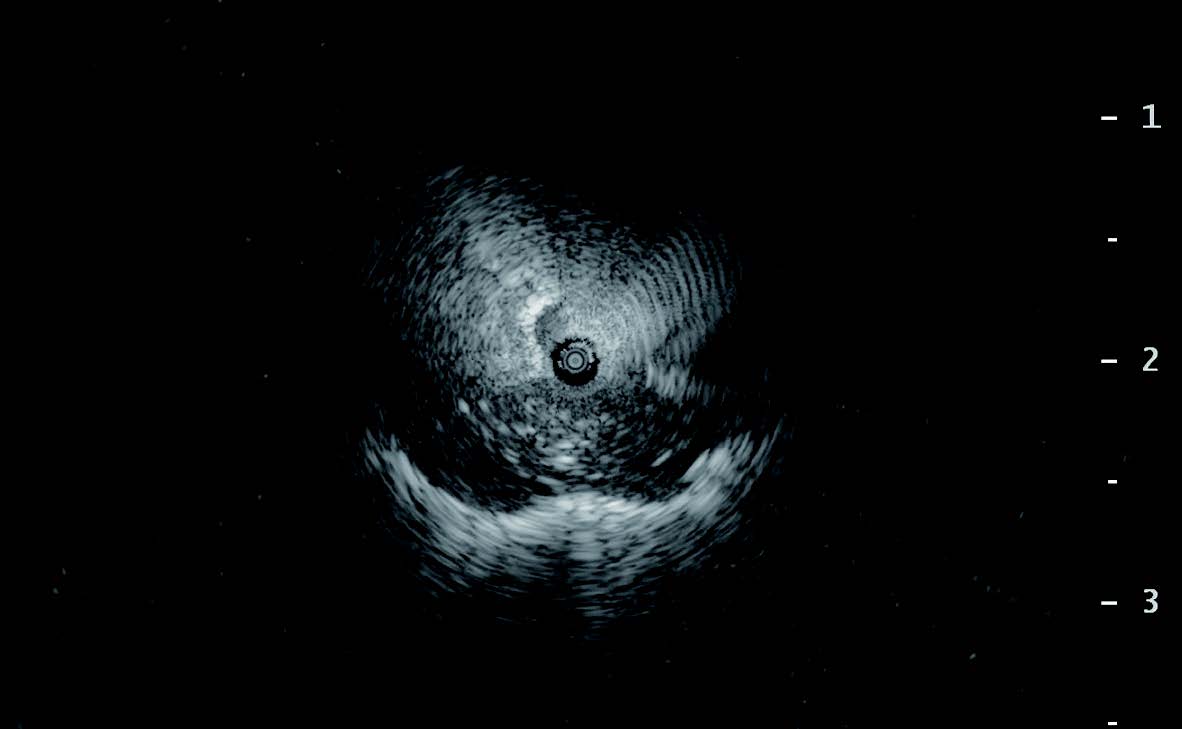

GuideSheath Kit 2は従来のガイドシースで時折みられたシースの折れやたわみが生じづらくなっている(Figure1)。特に、肺尖部やS6の病変は強く屈曲するため、従来ではガイドシースの折れが生じ、せっかくEBUSでwithinを描出したとしても、生検鉗子や擦過ブラシが途中で挿入できないこともあった。また、ガイドシースそのもののX線視認性も改善しており(Figure 2)、これらの改良は、検査時間の短縮のみならず、安全に検査が行えることに寄与している。また、BF-MP290Fや細径のGuideSheath Kit 2にも挿入可能な柔軟性のあるPeriView FLEXも開発され、末梢病変において穿刺が容易となった。

症例は左S3 aの結節であるが、明らかな関与気管支はなく、病変の前方上側に位置するB3 aiiの気管支が、もっとも病変に近い気管支であった(Figure 3)。BF-P290を使用し細径EBUS-GSを挿入したが、予想通りEBUS像がadjacent toであったため、EBUS-GS併用経気管支生検(EBUS-TBB)を4回施行した後に、留置したガイドシースにPeriView FLEXを挿入し、吸引針生検を2回行った(Figure 4)。X線透視で病変の中心に針があることが確認でき、その後のEBUSでwithinが得られたため、EBUS-TBBを3回追加できた(Figure 5)。本症例の最終診断は炎症性結節であった。

Figure 3. 症例 ltB3aii 結節影 BF-P290

Figure 4.